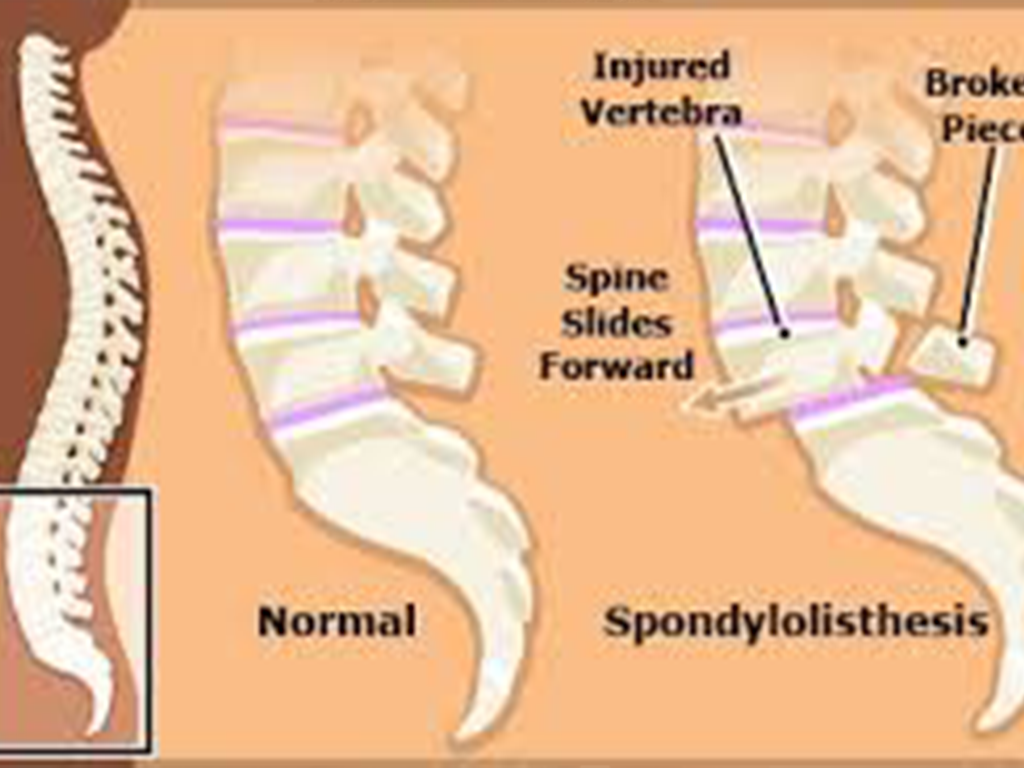

Hip replacement surgery involves replacing a damaged or worn-out hip joint with an artificial implant. This procedure is commonly recommended for patients suffering from severe joint pain or stiffness that does not respond to non-surgical treatments.

Patients visiting the Best Hospital for Hip Replacement in Gurugram Sector 52 often experience conditions such as osteoarthritis, rheumatoid arthritis, or hip fractures. The goal of the surgery is to relieve pain, restore movement, and improve overall quality of life.

This process includes reviewing the patient’s medical history, performing physical examinations, and conducting diagnostic tests such as X-rays or MRI scans. These assessments help determine the severity of joint damage and the most suitable surgical approach.